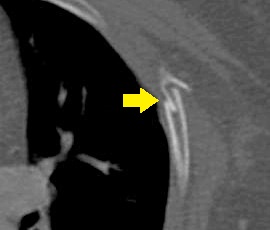

[肋骨骨折] 手術:肋骨骨折観血的手術

CT画像